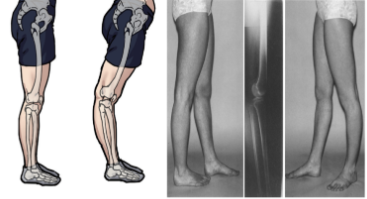

7.다리 변형이 신체에 미치는 영향

휜 다리는 단순한 미관상의 문제를 넘어 심각한 건강 문제를 유발할 수 있다.

정상적인 다리는 고관절에서 발목 관절까지 일직선을 이루며,

이 축이 무릎 가운데를 지나가야 체중이 고관절, 무릎 관절, 발목 관절에 고르게 분배된다.

1.오자형 휜 다리의 문제점

- 오자형으로 휜 다리는 무릎 안쪽에서 체중의 대부분을 지탱해야 하며,

이로 인해 무릎에 체중의 약 60%가 실리게 된다.

- 동양인의 경우, 선천적으로 무릎 관절에 가해지는 무게 중심이 정 가운데가 아닌

2~3mm 안쪽에 형성되어 있어, 무릎 안쪽 연골이 더 빠르게 닳아

O자형 휜 다리가 많이 발생한다.

이로 인해 무릎 안쪽 연골이 급격히 닳아 퇴행성 관절염의 진행이 가속화될 수 있다.

2. 건강상의 문제

- 오자형 휜 다리는 미관상 문제뿐만 아니라 건강에도 심각한 영향을 줄 수 있다.

- 무릎 관절에 과도한 부담이 가해져 퇴행성 관절염, 연골 손상 등의 문제가 발생할 수 있다.

또한 보행 및 균형 유지에 어려움을 겪을 수 있어 낙상 위험이 높아질 수 있다.